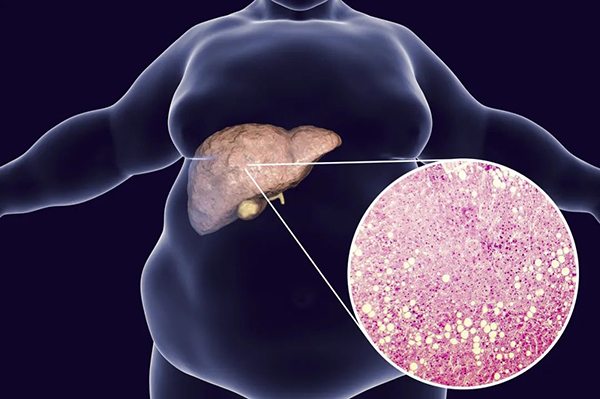

3.肥胖

脂肪肝已经成为现在中国最常见的肝病,城市发病率高达20-30%,已经把乙肝甩开几条街了。而脂肪肝的原因就更简单了,吃得多,运动少,脂肪在体内积累的时候,你不仅仅是肚大腿粗身材差,而且肝脏会第一个受害称为脂肪肝。即使有效控制肥胖引起的心脏病和脑血管疾病、糖尿病,脂肪肝还是会有发展成肝硬化和肝癌的机会的。而且,脂肪肝不像心脑血管疾病那么好治,现在还没有特效治疗药物,只能靠减肥!

图库版权图片,不授权转载